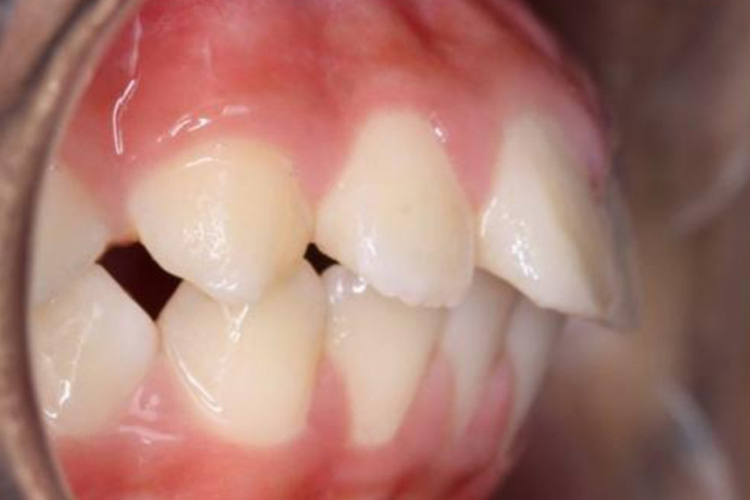

轻微上颌前突通常表现为上前牙及上唇轻微前突,呈凸面型。并且自然状态上下唇不能闭合,微笑时可露出小部分牙龈,闭唇时颏肌较为紧张,颏唇沟变浅或消失,前牙可出现轻微深覆合。